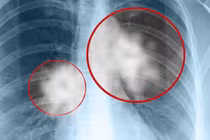

ThS.BS Nội trú Nguyễn Kim Anh cho biết, từ những dấu hiệu “không khớp” này, ê-kíp đã chủ động mở rộng chẩn đoán, chỉ định chụp CT xoang để loại trừ các bệnh lý vùng mũi xoang. Kết quả hình ảnh cho thấy tổn thương xoang hàm có đặc điểm gợi ý nhiễm nấm xâm lấn kèm theo dấu hiệu ăn mòn cấu trúc xương xoang.

Dựa trên lâm sàng và hình ảnh học, bệnh nhân được chẩn đoán nhiễm nấm đen xâm lấn xoang hàm (mucormycosis) – một bệnh lý hiếm gặp nhưng cực kỳ nguy hiểm, có khả năng tiến triển rất nhanh và đe dọa trực tiếp đến tính mạng.